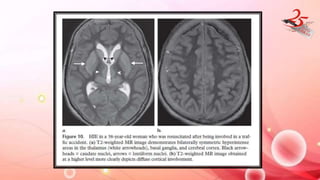

HYPOXIC ISCHEMIC ENCEPHALOPATHY

• CAUSE : Result of cardiac arrest /drowning/asphyxiation

IMAGING FINDINGS:

• Mild HIE : water shed zones

• Severe HIE : grey matter structures like cerebral cortex , BG and

hippocampi.

• Brainstem and WM are typically spared.

• CT : Diffuse edema , decreased attenuation of the cortical gray matter

with loss of normal gray matter–white matter differentiation, BG and

Thalamus

• WHITE CEREBELLUM SIGN : diffuse cerebral damage results in lower attn.

of cerebral parenchyma , compared to cerebellum and BG which are

spared – POOR PX

• Earliest finding(after 2 hrs) : Increased SI of the affected areas on

DW

• T2W : hyperintensity and swelling of affected areas ( after 24 hrs)

• Delayed : T2 hyperintensity in subcortical WM